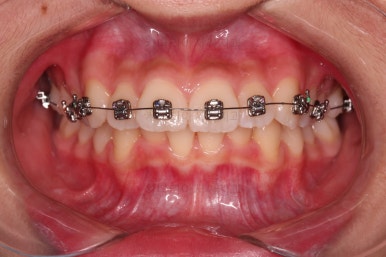

우선 윗니만 장치를 부착했습니다.

순서는 윗니 장치 부착 후 발치를 하고, 가지런하게 된 뒤에, 과개교합 개선을 위한 특별한 장치가 들어가면서 아랫니에도 브라켓을 부착하기로 정했습니다.

이번 환자분이 선택한 장치는 엠파워 메탈이라고 하는 자가결찰 금속 브라켓입니다.

장치를 부착한 직후의 얼굴 모습 변화와 장치가 보이는 느낌을 한 번 봐주시고요.